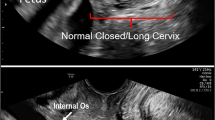

Schlembach D, MacKay L, Shi L, Maner WL, Garfield RE, Maul H. Cervical ripening and insufficiency: from biochemical and molecular studies to in vivo clinical examination. Eur J Obstet Gynecol Reprod Biol. 2009;144:S70–6. https://doi.org/10.1016/j.ejogrb.2009.02.036.

Schlembach D, Maul H, Fittkow C, Olson G, Saade G, Garfield R. Cross-linked collagen in the cervix of pregnant women with cervical insufficiency. Am J Obstet Gynecol. 2003;189:S70. https://doi.org/10.1016/j.ajog.2003.10.034.